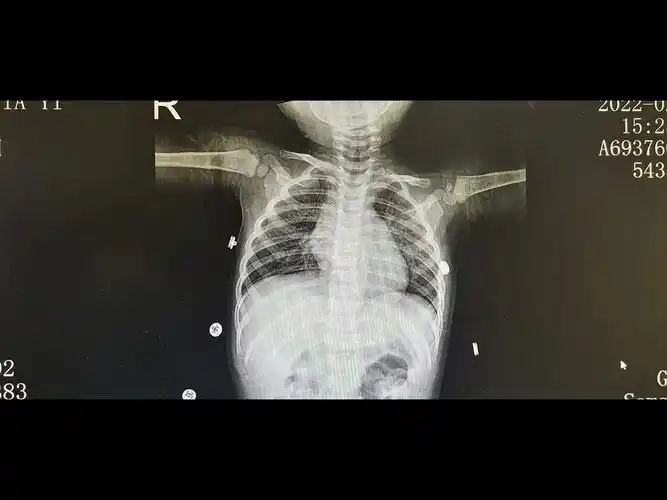

女童未及时就医诊断小儿支气管肺炎联合用药得以缓解